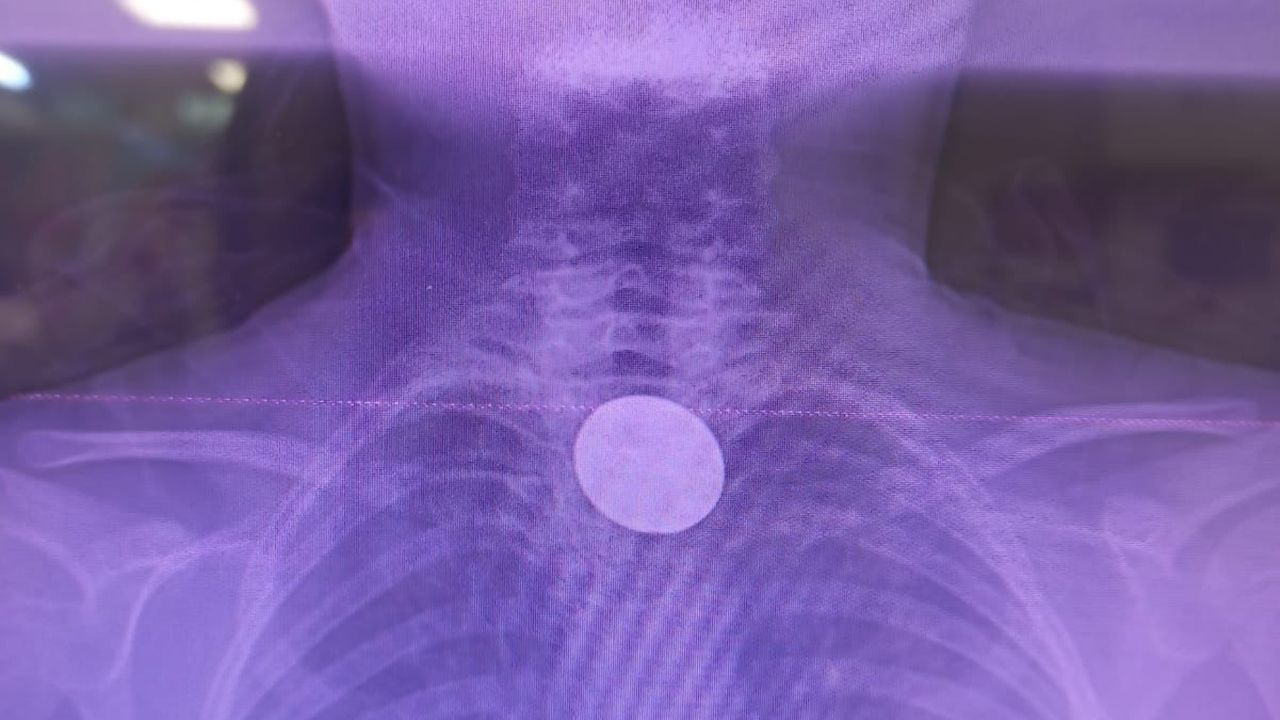

Yapılan incelemelerde 5 TL’lik madeni paranın Y.K.’nin yemek borusuna kadar ilerlediği belirlendi. Çocuk hastalarda ciddi solunum ve sindirim sistemi riskleri oluşturabilen bu durum üzerine ilgili branşlar vakit kaybetmeden harekete geçti.

Madeni paranın çıkarılması için Gastroenteroloji Uzmanı Dr. Yaren Dirik ile Kulak Burun Boğaz (KBB) Hekimi Dr. Yasin Gökçınar tarafından ortak bir girişim gerçekleştirildi. Alanında uzman ekiplerin koordineli çalışmasıyla madeni para herhangi bir komplikasyona yol açmadan başarıyla çıkarıldı.